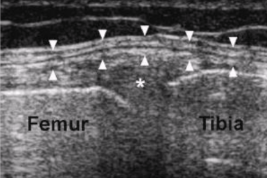

Articular cartilage

Found at terminal ends of bone at joints

Adheres to bone surface

Controls articular joint fluid level

Function - minimizes friction and aids in weight distribution and compression

Articular cartilage US appearance

Hypoechoic noncompressible layer in contact with bone surface